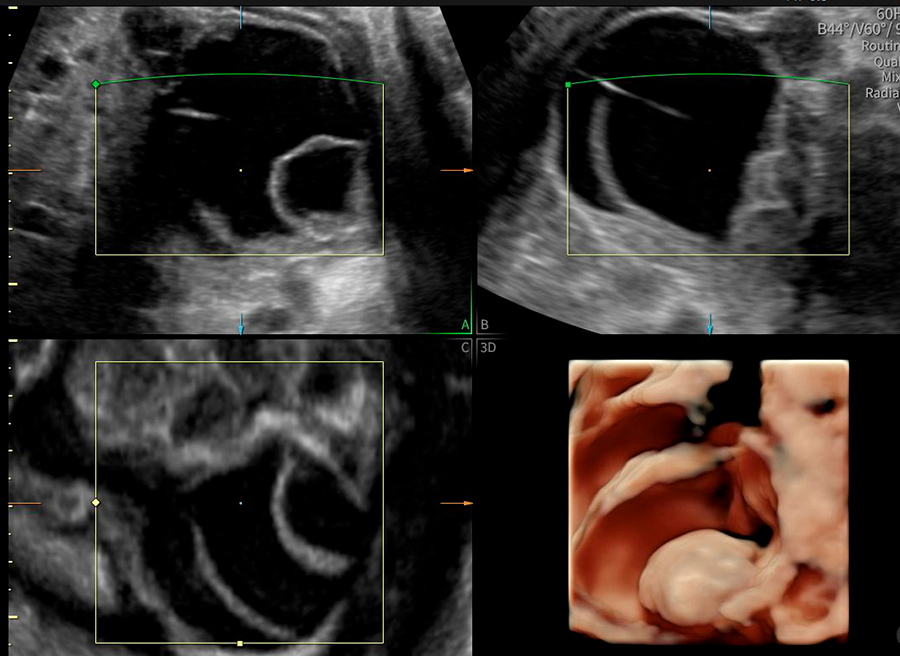

La ecografía ginecológica es un estudio por imágenes no invasivo que permite evaluar de forma precisa el útero, los ovarios y el sistema reproductor femenino. Es una herramienta fundamental para la detección temprana de alteraciones ginecológicas, el seguimiento de tratamientos y los controles preventivos.

En OBGYN Perú, realizamos ecografías ginecológicas con equipos de alta resolución, garantizando resultados confiables y una atención médica especializada.